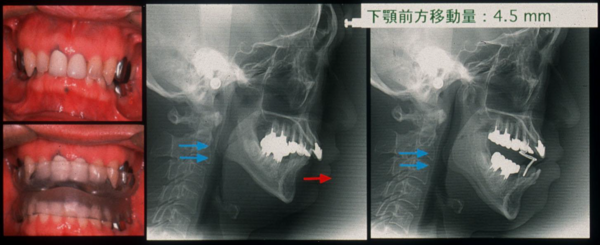

- 歯科装置:睡眠時に専用のマウスピースで下あごを数㎜前に引き出すことで、気道が潰れるのを防止する。